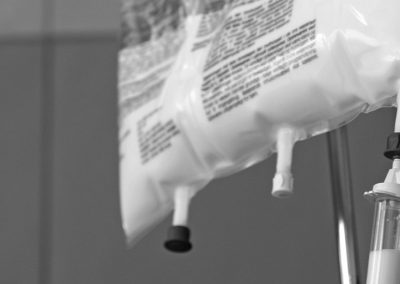

Aprovecha el conocimiento de profesionales sanitarios de referencia, con estos whitepapers podrás conocer de primera mano información relavante sobre técnicas y procedimientos.

Las primeras 72 horas de vida: Un momento crucial para la supervivencia y el bienestar del recién nacido

Whitepaper: Eficacia y seguridad del uso de un sistema no mecánico de presión positiva constante en la insuficiencia respiratoria hipoxémica en un servicio de urgencias. 117 casos.

Whitepaper: ¿Por qué la jeringa de bajo volumen (LDT) NO elimina los riesgos de sobredosis en neonatos?

Whitepaper: Comparativa entre dispositivos para ventilación vs dispositivos para oxigenación pasiva en RCP